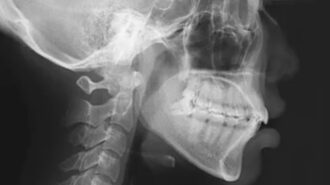

正畸病例

颌位重建病例

病例 解析